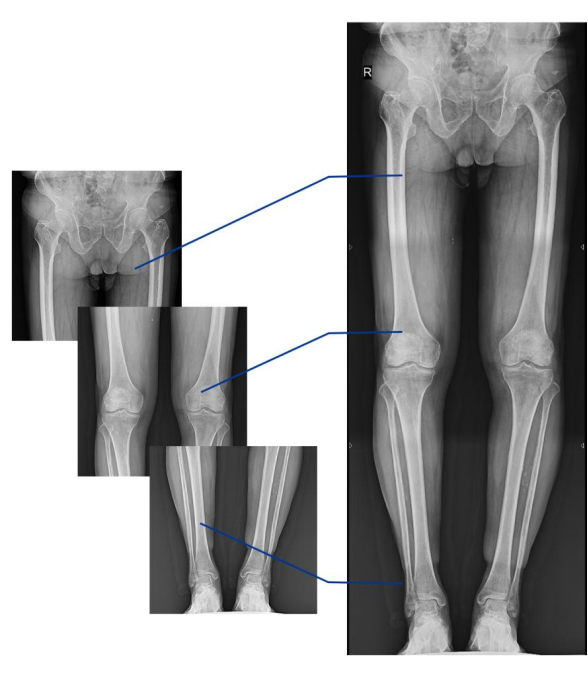

不同于常規(guī)靜態(tài)DR只能進行平片攝影檢查,動態(tài)DR可以滿足多種臨床檢查需求,包括靜態(tài)檢查、透視檢查、造影檢查、脊柱及下肢全長拼接檢查,相較于靜態(tài)DR具有豐富的臨床應用,且動態(tài)DR檢查更精準、直觀,擺位攝片效率極大地提升,大大節(jié)省拍片時間。

動態(tài)DR影像采集幅面大,17×17英寸超大視野,可覆蓋成年人的全胸全腹,并且能在連續(xù)動態(tài)中實時高清點片,還可以進行視頻保存,在會診過程中可以回放影像檢查視頻,從而達到精準診斷的目的。同時動態(tài)DR還具有全身拼接功能,尤其適用于全脊柱和全下肢攝影,輔助脊柱畸形矯形治療、康復檢查,為臨床提供高精度圖像。